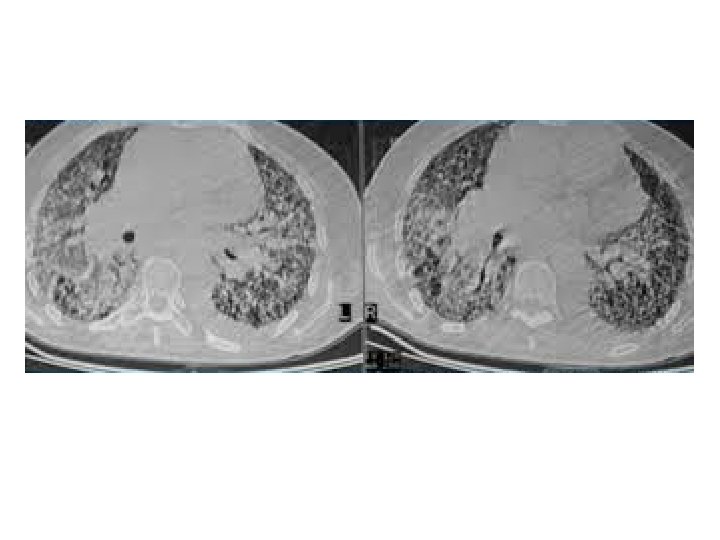

Acute Exacerbation of IPF (AE-IPF) • Episodes of sudden deterioration of a respiratory status • Can occur at any point in the course of IPF • Histologically ― DAD on a background of UIP Kondoh et al. Chest 1993

Acute Exacerbation of IPF (AE-IPF) ‘IPF Net Criteria’ • Previous or concurrent diagnosis of IPF • Worsening dyspnea of 30 days or less • New bilateral ground glass and/or consolidation (superimposed on IPF/UIP pattern on HRCT Chest) • No microbiological evidence of respiratory infection by endotracheal aspirate or BAL (if absent, can call ‘suspected acute exacerbation’) v Documentation of abnormal gas exchange has been removed Collard et al, AJRCCM 2007